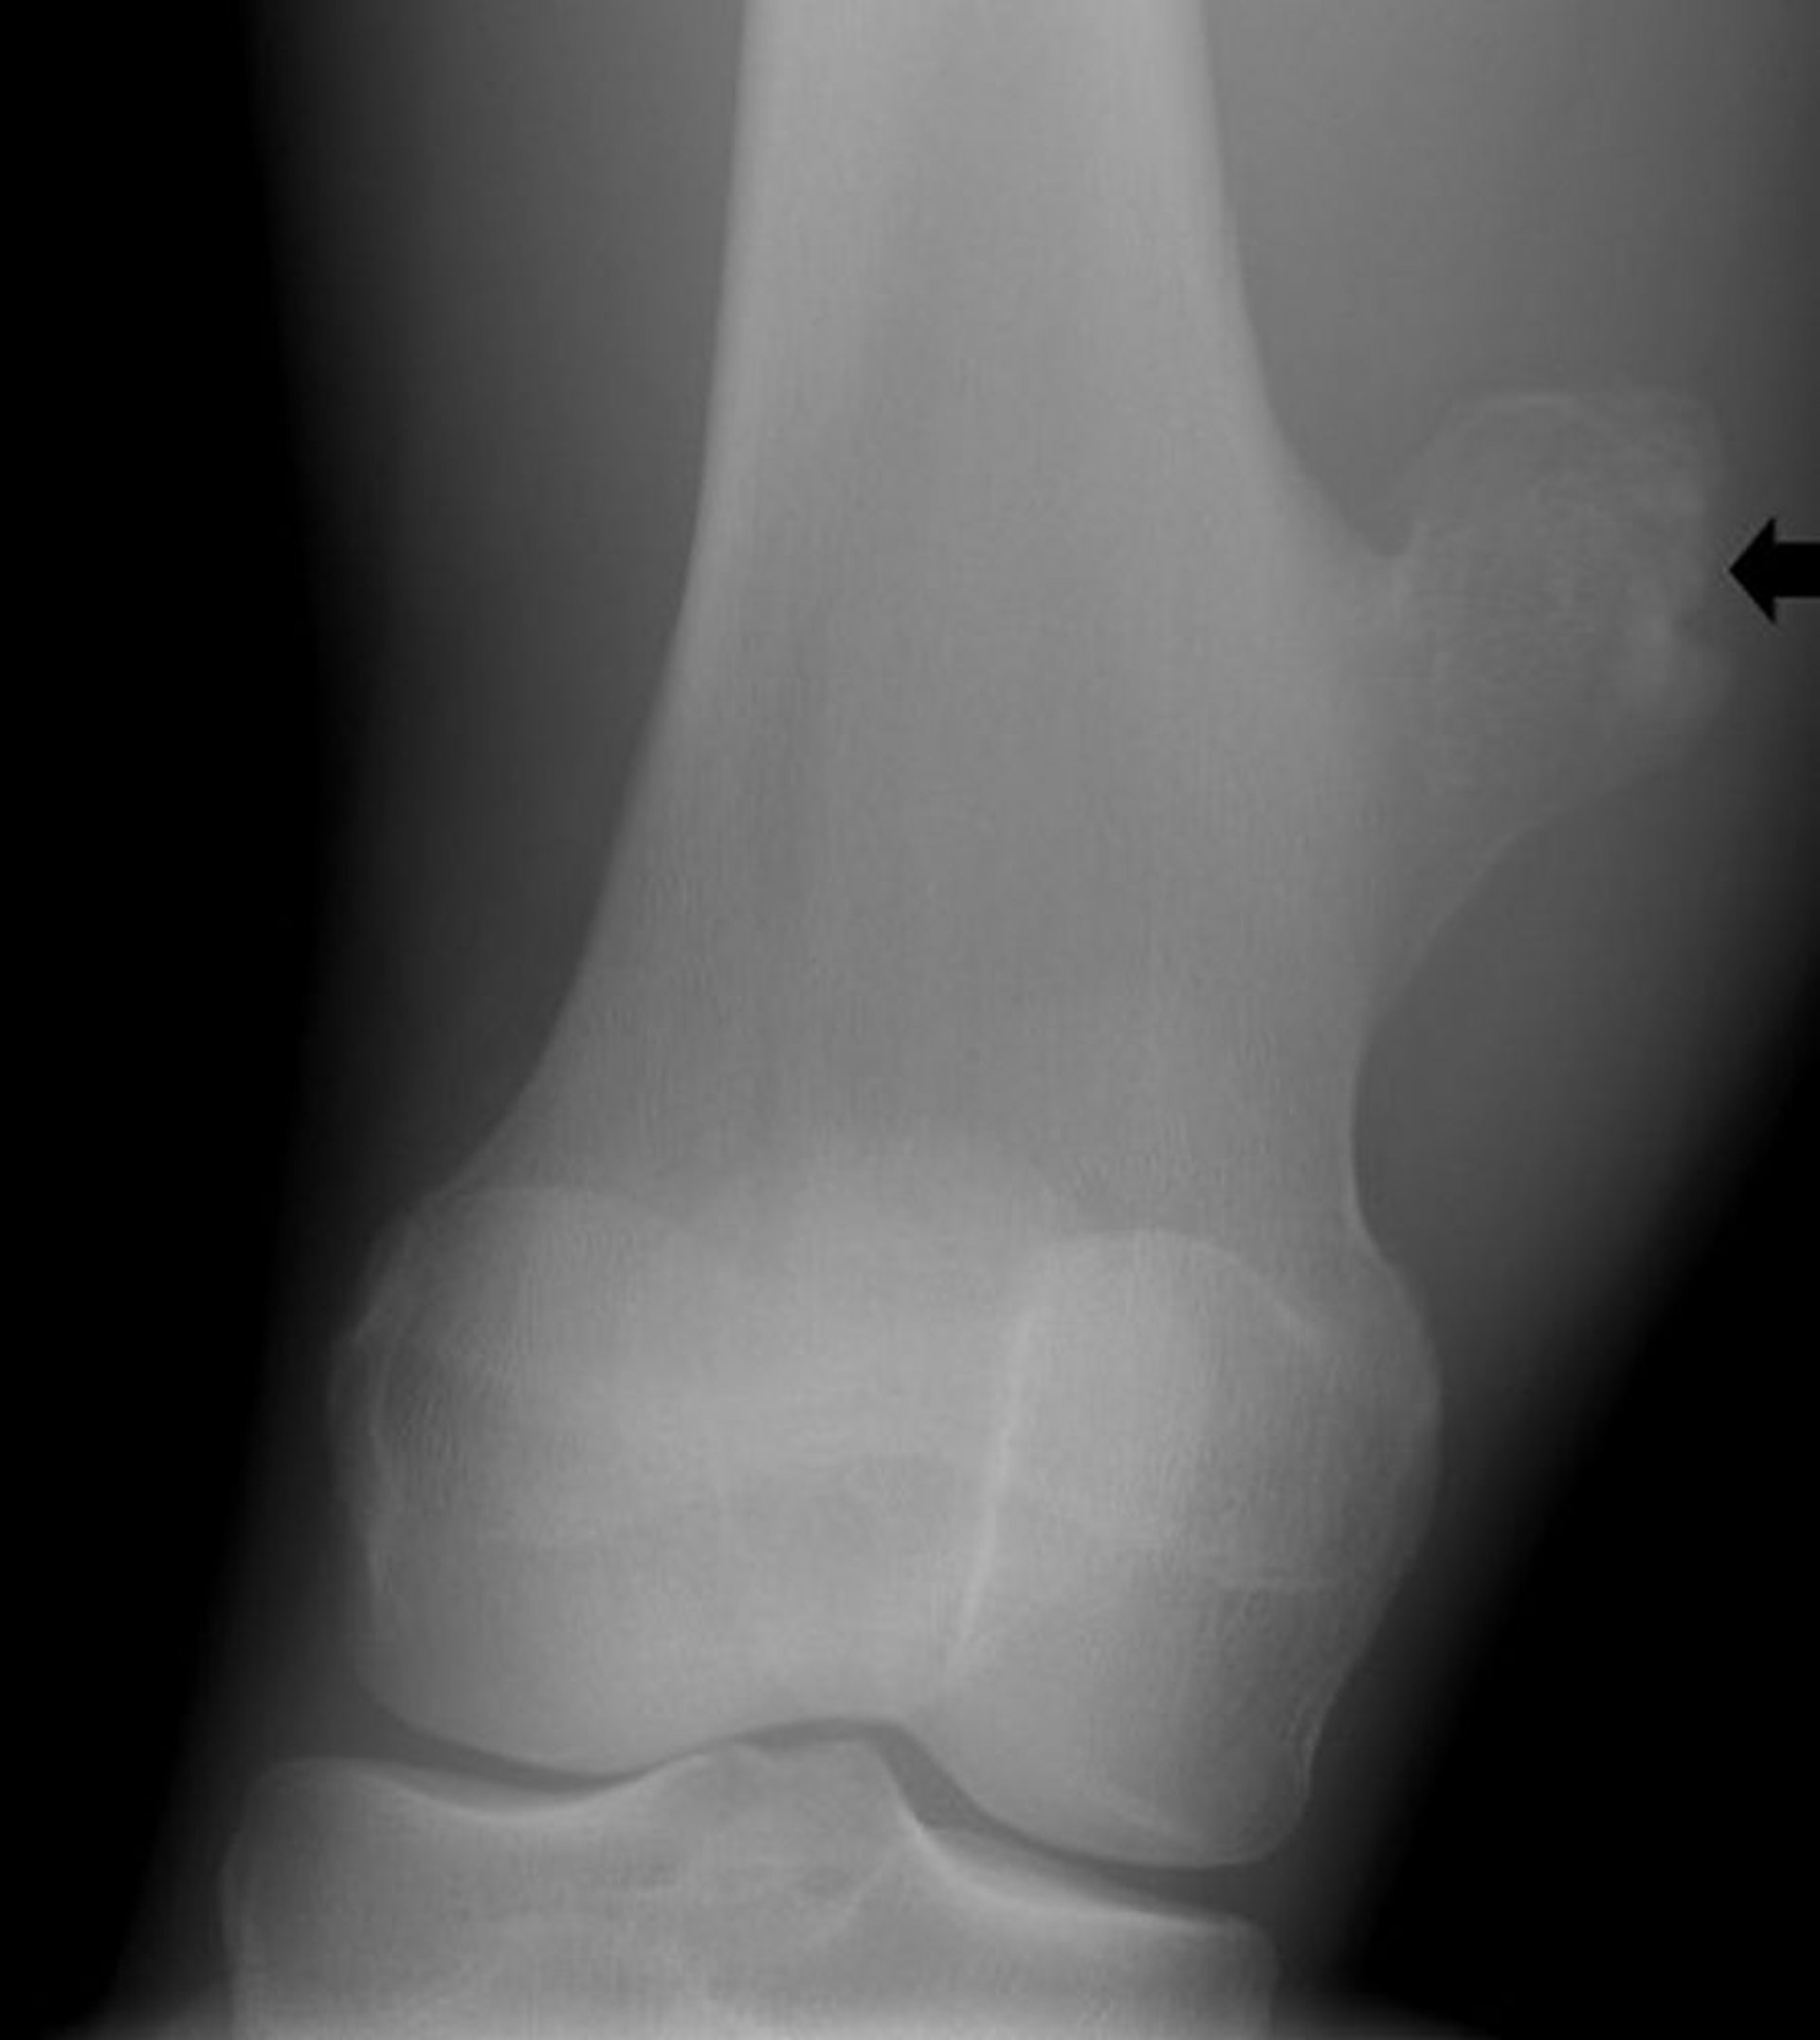

Osteocondroma del ginocchio

Questa radiografia del ginocchio mostra un'escrescenza ossea (freccia) dal femore sopra l'articolazione del ginocchio che è coerente con un osteocondroma.

Image courtesy of Michael J. Joyce, MD, and Hakan Ilaslan, MD.